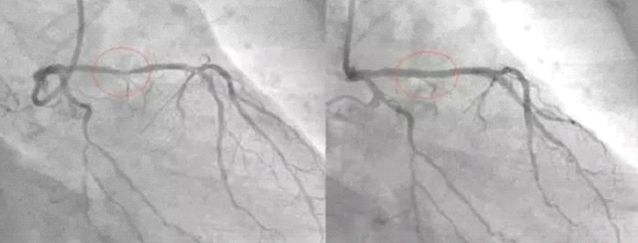

Hakim allowed him do a diet therapy at home, which he did for a month. A month later he went to the same hospital for an examination, he found out that three vessels were cleaned; the original heart attack place had all-pass. In order to allow more people get benefit, he shared his own experiences on the Internet. He put His before and after two vessels photos on the Internet, in the difference of photos taken before and after the diet therapy, even ordinary people could identify with it.